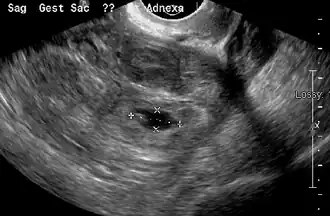

Transvaginal ultrasonography

An ultrasound showing a gestational sac with the fetal heart in the fallopian tube has a very high specificity for ectopic pregnancy. It involves a long, thin transducer, covered with the conducting gel and a plastic/latex sheath and inserted into the vagina.[38] Transvaginal ultrasonography has a sensitivity of at least 90% for ectopic pregnancy.[5] The diagnostic ultrasonographic finding in ectopic pregnancy is an adnexal mass that moves separately from the ovary. In around 60% of cases, it is an inhomogeneous or a noncystic adnexal mass, sometimes known as the "blob sign". It is generally spherical, but a more tubular appearance may be seen in the case of hematosalpinx. This sign has been estimated to have a sensitivity of 84% and a specificity of 99% in diagnosing ectopic pregnancy.[5] In the study estimating these values, the blob sign had a positive predictive value of 96% and a negative predictive value of 95%.[5] The visualization of an empty extrauterine gestational sac is sometimes known as the "bagel sign", and is present in around 20% of cases.[5] In another 20% of cases, there is visualization of a gestational sac containing a yolk sac or an embryo.[5] Ectopic pregnancies where there is visualization of cardiac activity are sometimes termed "viable ectopic".[5]

Ultrasound image showing an ectopic pregnancy where a gestational sac and fetus have been formed